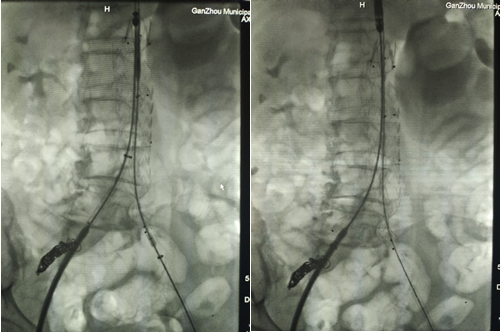

9、主體支架和左右分體支架釋放后,發(fā)現(xiàn)支架貼合不佳,球囊后擴(kuò)

10、在3D打印血管的輔助下完成腹主動(dòng)脈瘤的覆膜支架腔內(nèi)隔絕術(shù),最后造影結(jié)果